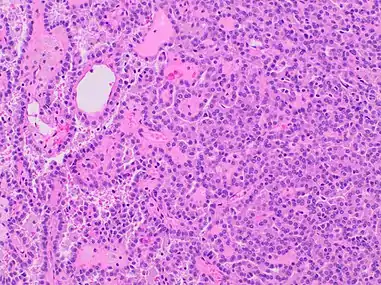

Type 1 PRCC, also known as a renal tumor caused by a genetic predisposition of hereditary papillary renal cancer syndrome, compromises approximately 25% of all PRCCs.[14][15] In the perspective of immunochemistry, it has a profile of strong CK7 and alpha-methyl acyl-CoA racemase (AMACR) expression at most focal CA-IX expression.[16] Histologically, its epithelium is composed of relatively small-sized simple cuboidal cells lined in a single layer.[17] These cells are well-characterized by basophilic cytoplasm.[18] Due to its solid growth, an extremely compact papillary architecture is often observed.[16] Other morphological characteristics include intracellular hemosiderin and foamy macrophages placed inside of papillary fibrovascular cores or psammoma bodies.[19] In general, the nuclei of type 1 PRCC belong to grade 1-2 of the Fuhrman system.[16]

A micrograph of type 1 PRCC, illustrating features of small basophilic cells with scarce cytoplasm. A single layer of cells are surrounding the basal membrane.[20] Foamy macrophages are inside of papillary fibrovascular cores.

Type 1 PRCC, this case being more compact at right.